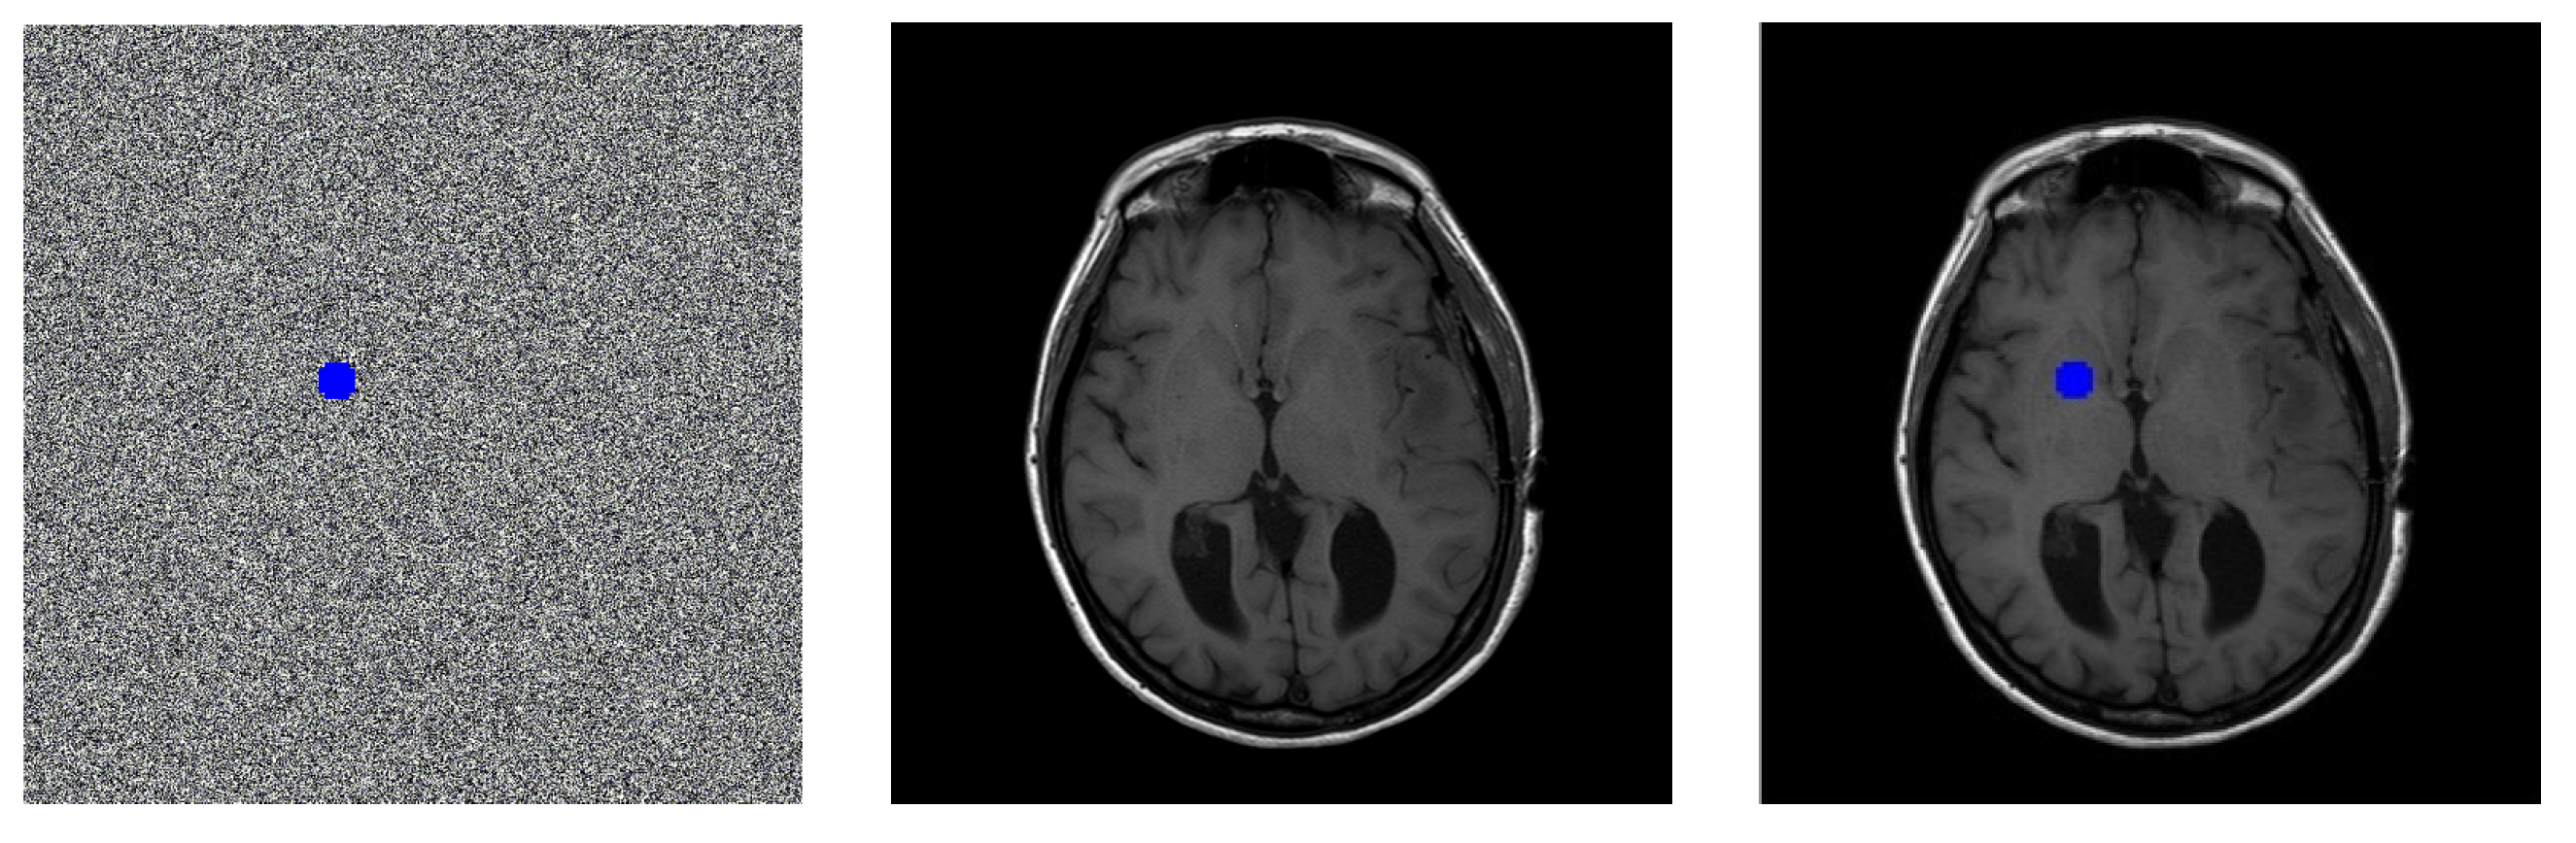

From the description of the proposed scheme, we know that the user can verify the integrity of ROI for the restored image, and locate the position of the tampered image. In order to give a total understanding of tampers localization, the example illustrates the verification process for the restored image.

For example, for the second sharing secret image generated from image IM-0001-0012, see the image block in blue color in Figure 8(a), the first pixel value is changed to 111 from the original value 106; the second pixel is changed to 100 from 97. Obviously, the sharing secret is tampered. Next the tampered image block will be located.

Firstly, the two sharing secrets are decrypted, and then hashes of the original image blocks are extracted, the data is represented by H i , i = 1,2 , N . N is the total number of block.

Secondly, conduct the superposition of two sharing secret to produce one image by plus the pixels of the corresponding position, and then carry out the reversible substitution of S-box for the ROI. The restored image is shown in Figure 8(b).

Lastly, for the restored image, calculate the hashes of every block in ROI, these values are marked by H i r , i = 1,2 , N It is found that the hash value of H 253 is different from the value of H 253 by comparing H i , i = 1,2 , N and H i r , i = 1,2 , N ,:

H 253 =   2A6692938C21F29A8351F6CEAD689398

H 253 = 69C19839984065D2A0D4DFFF776629CB

Thus, the tampered part is located, which is shown in blue color in Figure 8(c).

It can be seen that the original image is not losslessly restored, although there is no clear visual difference between the restored image and the original.

Figure 8. Example of tampers localization of restored image.

Preprints 80000 g008